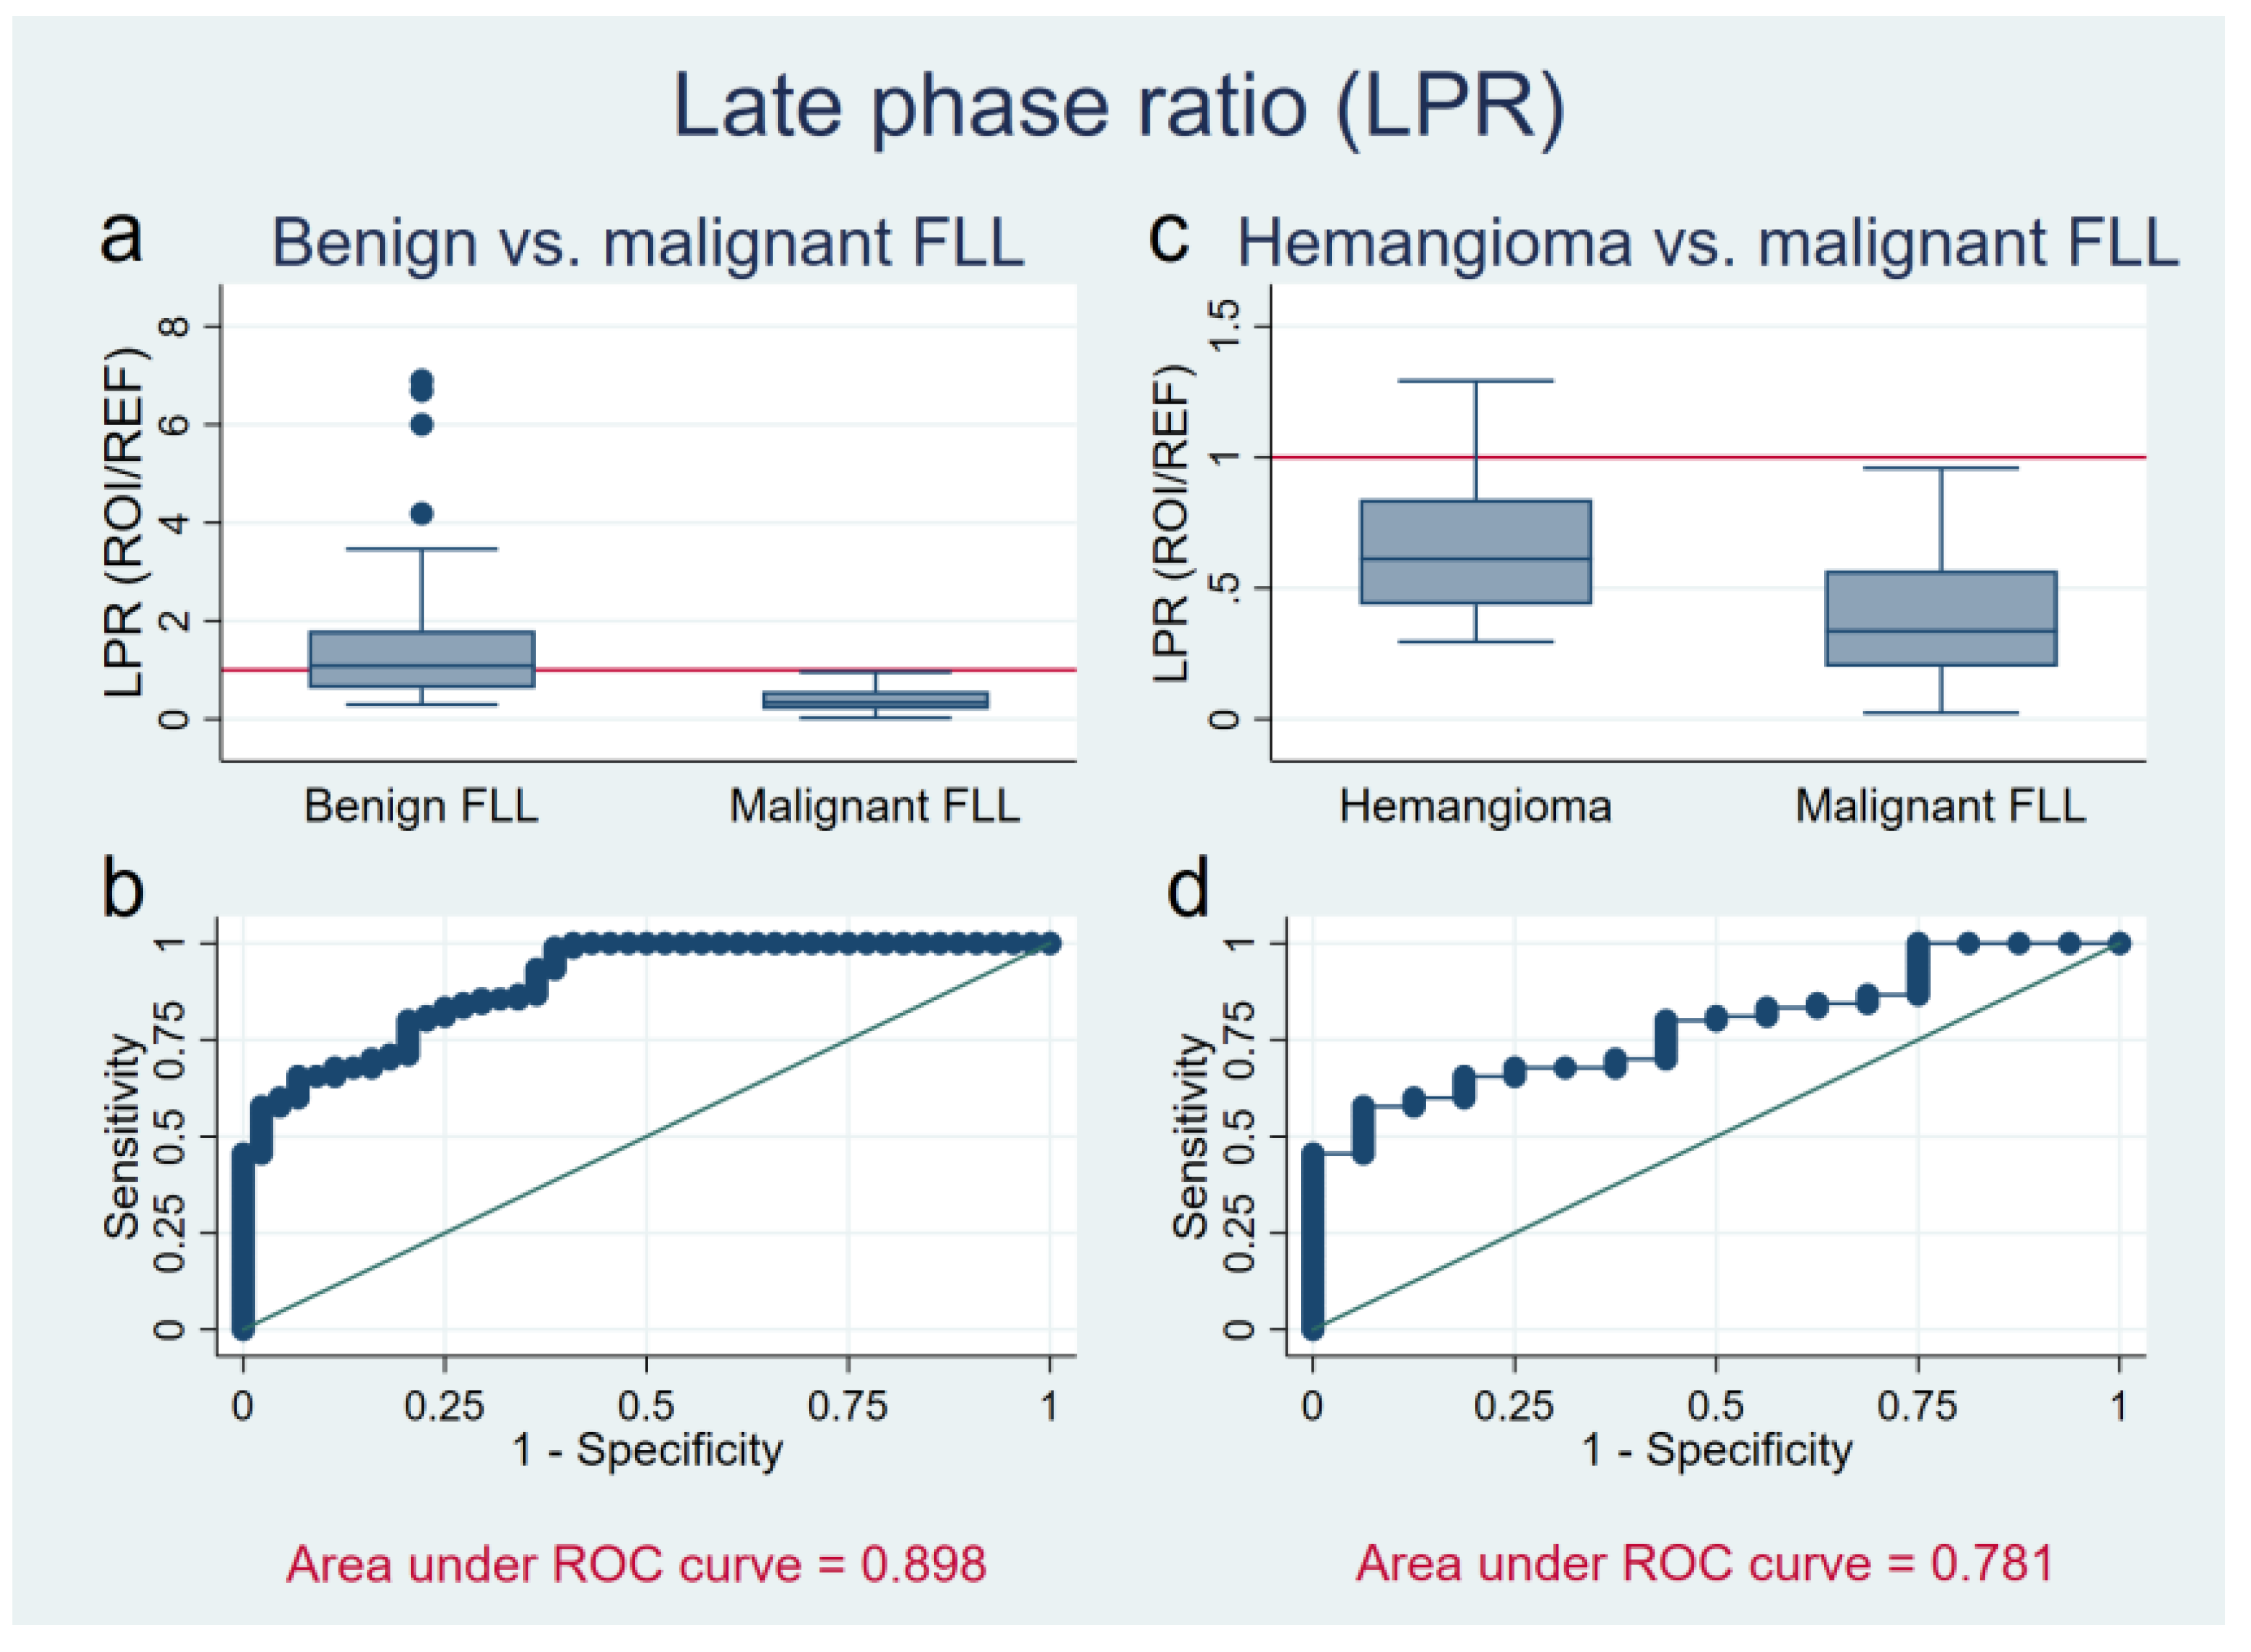

3.2. Late Phase Ratio